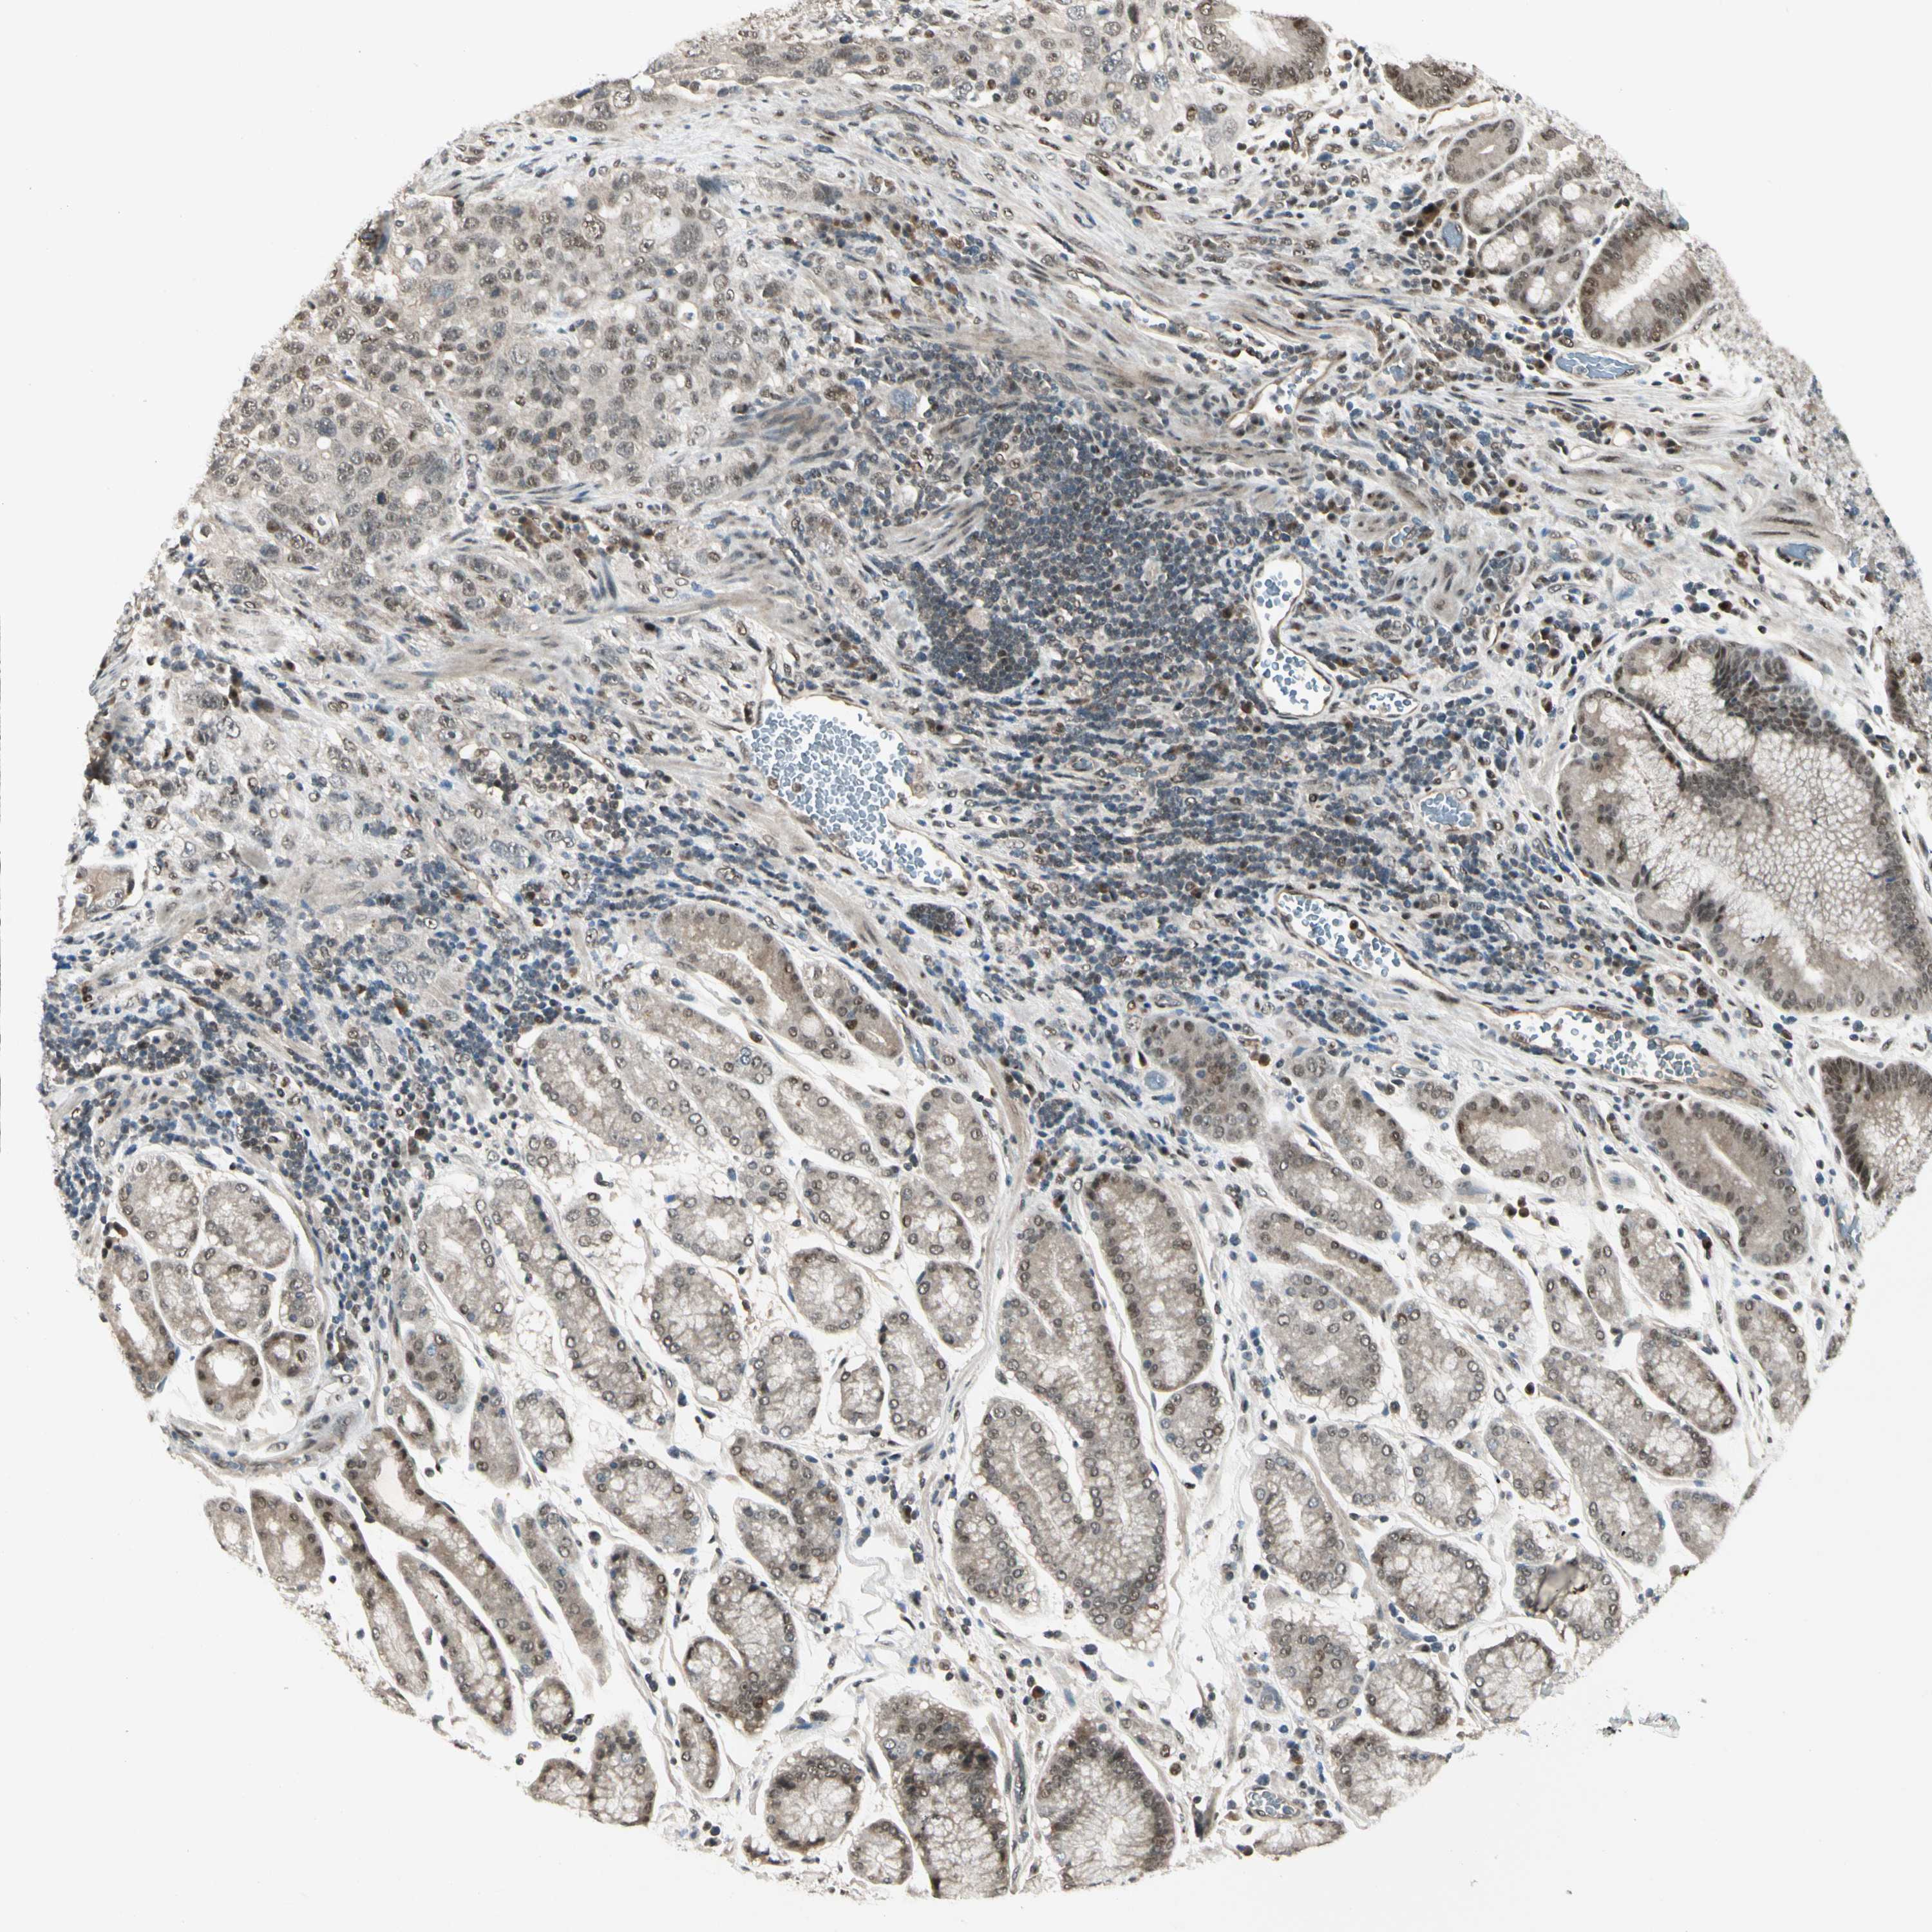

STOMACH CANCER - Protein expressioni

A mouse-over function shows sample information and annotation data. Click on an image to view it in a full screen mode. Samples can be filtered based on level of antibody staining by selecting one or several of the following categories: high, medium, low and not detected. The assay and annotation is described here.

Note that samples used for immunohistochemistry by the Human Protein Atlas do not correspond to samples in the TCGA dataset.

Antibody stainingi

Antibody staining in the annotated cell types in the current human tissue is reported as not detected, low, medium, or high, based on conventional immunohistochemistry profiling in selected tissues. This score is based on the combination of the staining intensity and fraction of stained cells.

Each image is clickable and will lead to virtual microscopy that enables deeper exploration of all samples and also displays staining intensity scores, fraction scores and subcellular localization as well as patient and tissue information for each sample.

Antibody HPA007990

Staining

High

Medium

Low

Not detected

Intensity

Strong

Moderate

Weak

Negative

Quantity

>75%

75%-25%

<25%

None

Location

Nuclear

Cytoplasmic/membranous

Cytoplasmic/membranous,nuclear

Adenocarcinoma, NOS